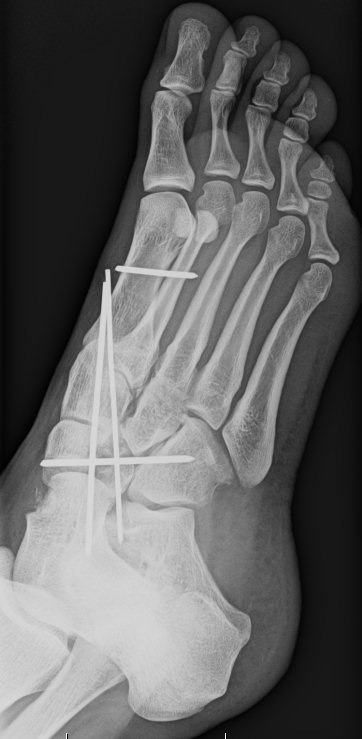

Kriplíci, úrazy, zranění a simulace